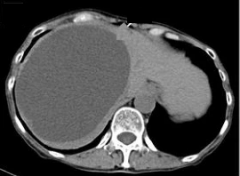

病史 50 岁的女性 由于之前进行过盆腔手术,所以出现了多个增大的子宫肌瘤以及腹膜内囊肿的情况。 已经持续數月遭受嚴重的骨盆疼痛之苦。 药物治疗 盆腔冠状位 T2 加权磁共振成像:多发子宫肌瘤及腹膜内囊肿。 治疗方案选择 由于存在粘连,子宫切除手术无法...